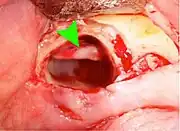

Pericoronitis is an infection of the operculum of a partially impacted wisdom tooth. It can be treated with local cleaning, an antiseptic rinse of the area and antibiotics if severe. Definitive treatment can be excision of the operculum, however, recurrence of these infections is high. Pericoronitis, while a small area of tissue, should be viewed with caution, because it lies near the anatomic planes of the neck and can progress to life-threatening neck infections.[14]: 440–441

Wisdom teeth removal

Wisdom teeth removal (extraction) is the most common treatment for impacted wisdom teeth. In the US, 10 million wisdom teeth are removed annually.[20] The procedure can be either simple or surgical, depending on the depth of the impaction and angle of the tooth. Surgical removal is to create an incision in the mucosa of the mouth, remove bone of the mandible or maxilla adjacent the tooth, extract it or possibly section the tooth and extract it in pieces. This can be completed under local anaesthetic, sedation or general anaesthetic.[5] As of 2020, the evidence is insufficient to recommend one type of surgical practice over another.[21]